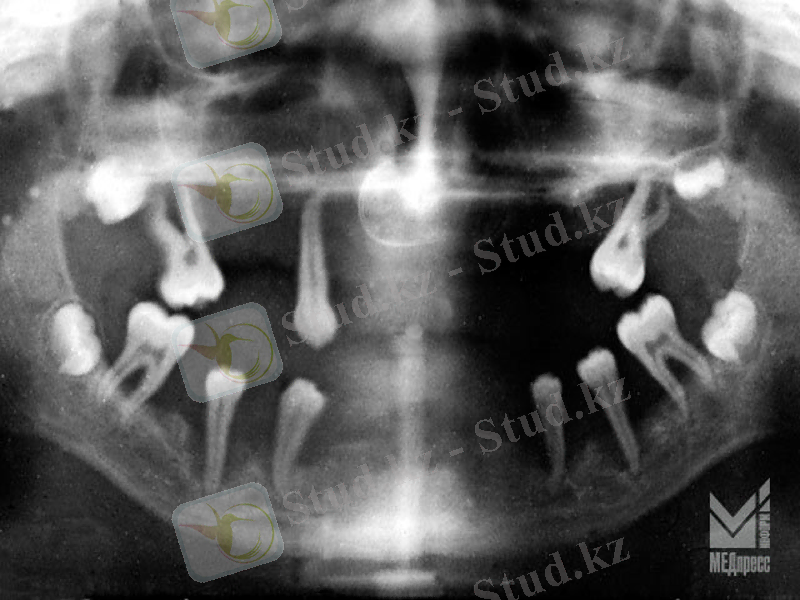

Рентген суретте: периодонт саңылауының жиектік бөлігі кеңейгені анықталды.

Альвеола сүйегінің жедел сорылуымен, созылмалы түрінде көптеген тістер аймағына таралумен сипатталады. Сүйек тінінің жойылуы сүйектің тігінен және көлденеңінен сорылуымен кездеседі. Тістер ерте қозғалмалы болады. Көбінесе жүйелі аурулармен ассоциациялауға болады. Олар: қант диабеті, Даун синдромы, және пародонттың әртүрлі идиопатиялық аурулары.

Рентгендік суретте:Альвеола өсіндісінің парадонт қабынуы бар аймағында тістер аралық қалқан сүйектер ұштарын жауып тұрған тығыз сүйек қабатының ошақты сорылуы нәтижесінде бүтіндігі бұзылғаны немесе толығымен сорылып, кемік сүйек кеуектене бастағанын анықталады. Сүйек тіні сорылып, сүйек биіктігі біраз 1/3 биіктігіне төмендеуі нәтижесінде алдыңғы тістер аралық қалқандар пішіні кертілген конусқа ұқсап қалады, кемік сүйекте ошақты немесе жайыла кеуектену үрдісі орын алады. Компактты пластинканың деструкциясы. Тістердің мойын бөлігінде периодонт саңылаулары кеңейгені байқалады.

Рентгендік суретте: Тістер аралық қалқан сүйектер түбір ұзындығының 1/3-1/2 бөлігіне дейін біркелкі емес көлденең сорылған, сақталған бөліктеріндегі кемік сүйекте жайыла кеуектену үрдісі орын алған. Периодонт саңылауы кеңейіп, сүйек қалталары пайда болған.